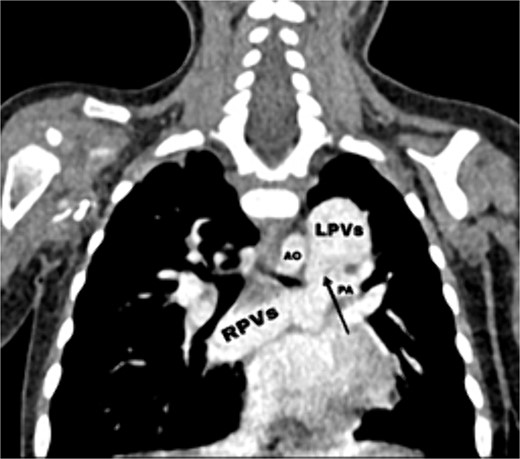

Transthoracic echocardiography (TTE) revealed an isolated supracardiac type of TAPVC, accompanied by a large ostium secundum atrial septal defect (ASD) measuring 9 mm, exhibiting a right-to-left shunt. Furthermore, there was evidence of dilatation in the right heart cavities and severe pulmonary hypertension (PHT = 65 mmHg). The common pulmonary confluence, measuring 12 mm in diameter, drained into the left innominate vein via a vertical vein. Confirmatory computed tomographic angiography (CTA) supported the diagnosis of supracardiac type TAPVC and identified stenosis along the venous pathway between the right and left pulmonary veins (Figs 1 and 2).

CT scan showing the right pulmonary veins (RPVs) and left pulmonary veins (LPVs) join all together posterior to the left atrium (LA) and pulmonary artery (PA), also showing the stenosis within the venous confluence between the drain of the right pulmonary veins and the drain of the left pulmonary veins.